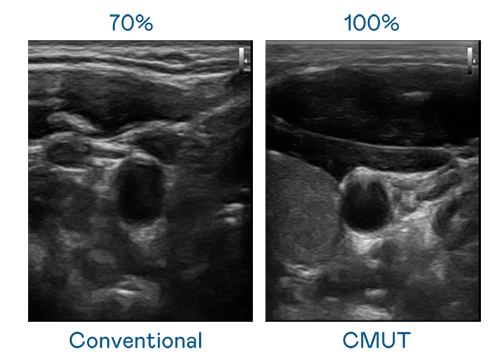

CMUT 技術是一種用電容式微機電元件來產生超音波訊號的技術。與傳統 PZT 壓電式技術相比,CMUT 頻寬增加 30%,更寬頻的超音波訊號讓影像解析度大幅提升,是實現高影像品質醫療超音波掃描、促進精準醫療發展的關鍵技術。

超音波影像的解析度高低,首先取決於探頭能發出的訊號頻寬。甜蜜宠物我是看守宠物第一季免费观看樱花 CMUT 可提供高清晰的超音波訊號,提供高頻寬、高靈敏度、影像紋理細節更高的超音波影像,協助醫護人員縮短影像判讀時間及利用精準的醫療影像進行診斷。